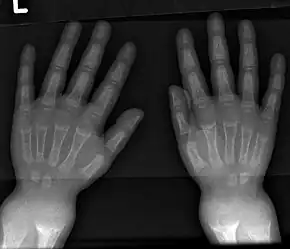

An X-ray or radiograph of an advanced patient with rickets tends to present in a classic way: the bowed legs (outward curve of long bone of the legs) and a deformed chest. Changes in the skull also occur causing a distinctive "square headed" appearance known as "caput quadratum".[18] These deformities persist into adult life if not treated. Long-term consequences include permanent curvatures or disfiguration of the long bones, and a curved back.[19]

- Radiography typically show widening of the zones of provisional calcification of the metaphyses secondary to unmineralized osteoid. Cupping, fraying, and splaying of metaphyses typically appears with growth and continued weight bearing.[47] These changes are seen predominantly at sites of rapid growth, including the proximal humerus, distal radius, distal femur and both the proximal and the distal tibia. Therefore, a skeletal survey for rickets can be accomplished with anteroposterior radiographs of the knees, wrists, and ankles.[47]